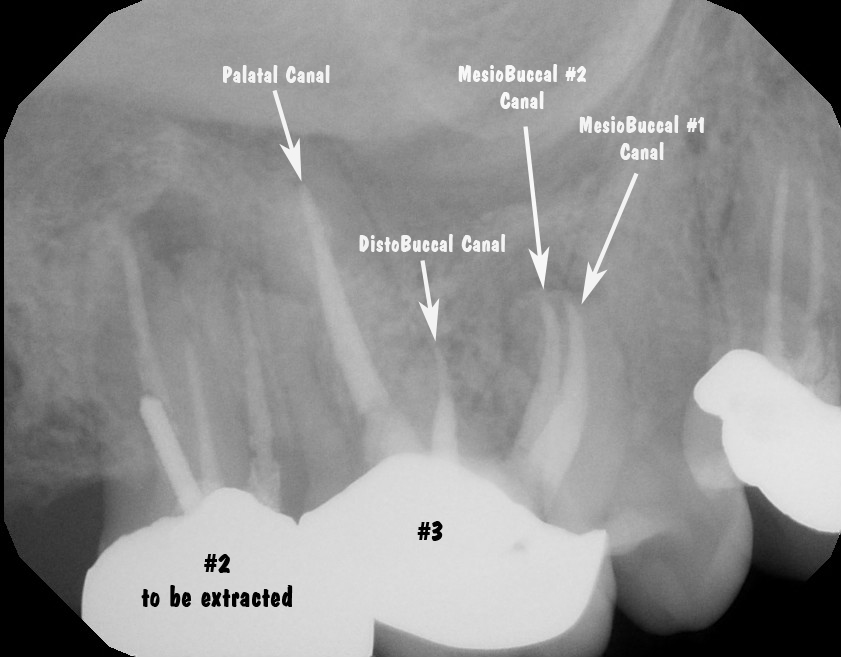

Endodontic diagnosis, including CBCT, determines that tooth #2 has a prior root canal with a root fracture and extraction is recommended.  Tooth #3 has a prior RCT with apical abscess - caused by a missed MB#2 canal during the initial root canal treatment.  Retreatment of the root canal #3 is recommended.

Endodontic retreatment with microscope locates the previously missed MB#2 canal.

PostOp radiograph shows all 4 canals have been properly treated.

PeriApical RadioLucency (PARL) seen at apex of MB root - which had a missed canal on initial treatment.

A common reason for root canal failure on Mx molars is inadequte cleaning, and often completely missing the MB#2 canal.  Endodontists using an operating microscope are able to find and treat the MB#2 (4th canal) more effectively and efficiently.  Endodontist are also trained to perform endodontic microsurgery when traditional endodontic therapy is unsuccessful.